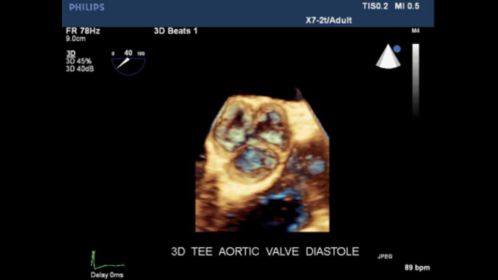

Http Asecho Org Wordpress Wp Content Uploads 2017 10 Ase Echoflorida 2017 3d Cropping Acquisition And Display Finalv3 Pdf